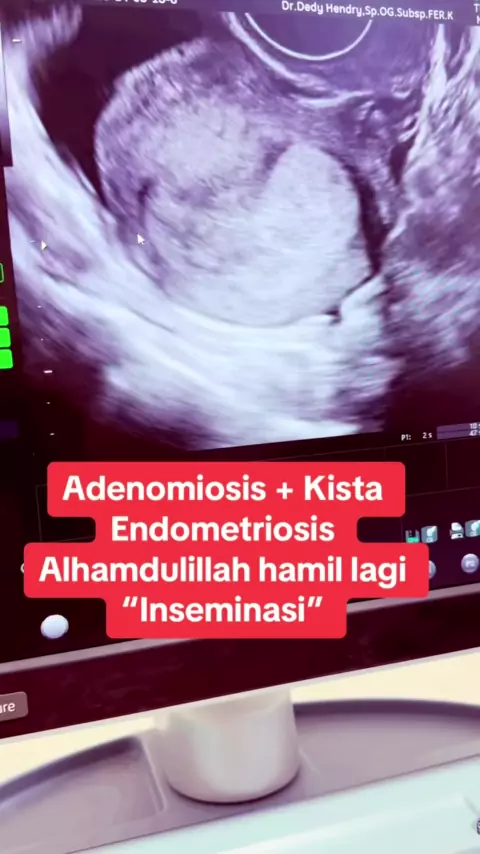

musuh terberat kesuburan adalah Adenomiosis dan kista endometriosis… Alhamdulillah bisa hamil lagi beberapa pasien kita semua atas ijin dan kuasa Allah.. alhamdulillah @klinikdesani @Morula IVF Padang #endometriosis #adenomiosis #inseminasiintrauterine #edukasidokterdedy #praktekdokterdedyhendry